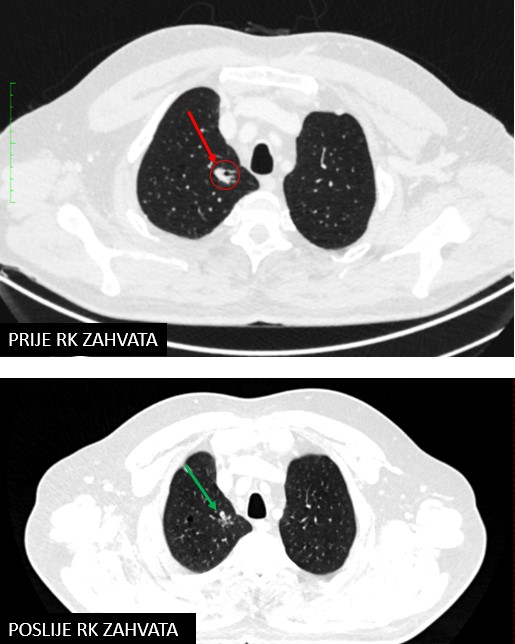

SABR meta pulmonis (13.10.2022.)

Rezultat – 6 mjeseci nakon RK

potpuni nestanak tretirane lezije uz vidljive postiradijacijske promjene